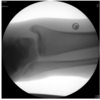

40-årig mand med ischias-symptomer. MR viser:

- a. Stor discusprolaps

- b. Absces

- c. Tumor

- d. Hæmatom

- e. Fremmedlegeme

*c. Tumor